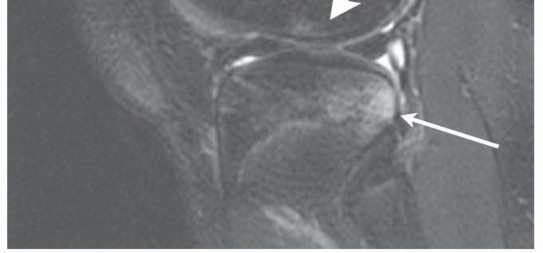

Most of the longitudinal growth of the lower extremities comes from the distal femur and the proximal tibia. The tibial physis can be as close as 15 to 20 mm to the tibial spine. The femoral physis comes within millimeters of the femoral attachment of the ACL at the most posterior aspect of its insertion (

FIG 1

).

FIG 1 • Sagittal MRI demonstrating the relationship of the ACL to the distal femoral and proximal tibial physes. (From Kocher MS, Garg S, Micheli LJ. Physeal sparing reconstruction of the anterior cruciate

*

ligament in skeletally immature prepubescent children and adolescents. Surgical technique. J Bone Joint Surg Am 2006;88[suppl, 1 pt 2]:283-293.)